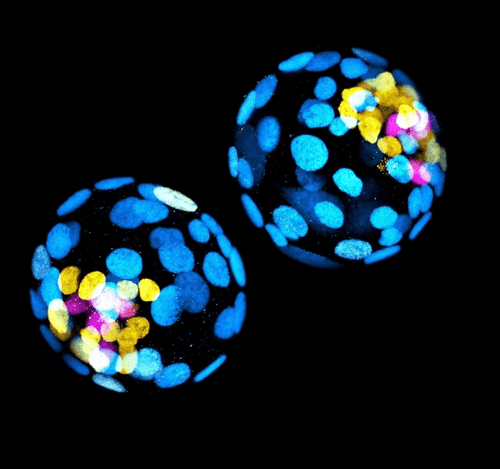

Generan embriones humanos sin óvulos ni espermatozoides

Parece una película de ciencia ficción pero es realidad: un equipo científico generó embriones humanos sintéticos sin óvulos ni espermatozoides. ¿Cómo lo hizo? Utilizando células madre.

Los científicos que lograron esta hazaña están liderados por el equipo de la Universidad de Cambridge (Reino Unido) y del Instituto Tecnológico de California (EEUU) y dirigido por Magdalena Zernicka-Goetz, la misma que publicó el pasado mes de agosto en la revista Nature cómo habían logrado reproducir fuera del útero y sin utilizar óvulos y espermatozoides lo que ocurre en las primeras etapas del desarrollo de un ratón.

«Afirman que han logrado embriones modelo, similares a los que se encuentran en las primeras fases del desarrollo humano, y que con este adelanto científico podrían encontrar respuestas a la hora de investigar los trastornos genéticos y las causas de los abortos espontáneos. Sin embargo, el trabajo viene acompañado de problemas éticos y legales», advierte Diario Médico.

En la presentación durante la conferencia de Boston, «Zernicka-Goetz describió el cultivo de embriones hasta una etapa un poco más allá del equivalente a 14 días de desarrollo para un embrión natural. En la actualidad, la ley del Reino Unido permite que los embriones humanos se estudien en el laboratorio solo hasta el día 14 de desarrollo».